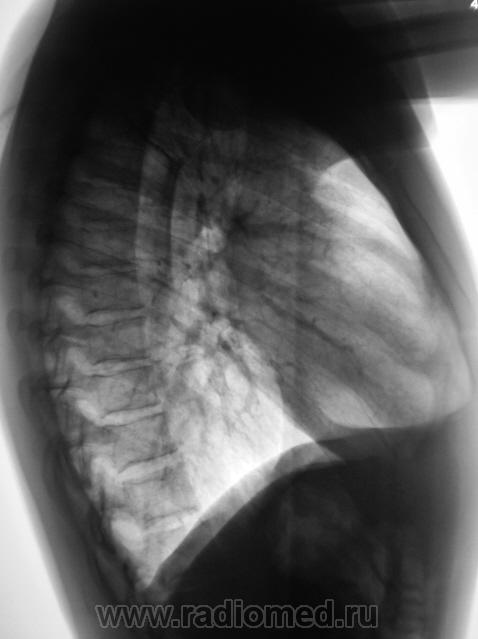

Произведена рентгенография в прямой и боковой проекциях.

Обнаружен "житель" в правом косто-диафрагмальном синусе.

Поставил за экран, и покрутил - следует за диафрагмой, в оптимальной проекции "на контур" выходит как "полусфера".